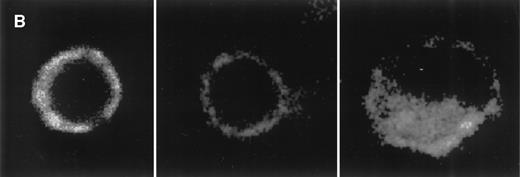

To examine whether the reduction of CCR5 mRNA expression induced by cAMP elevating agents was paralleled by a concomitant downregulation of surface CCR5 expression, we performed flow cytometry studies using a monoclonal anti-CCR5 antibody (Fig 3A). Pretreatment of monocytes with PGE2 for 48 hours showed more than 55% reduction of CCR5 protein expression (mean fluorescence PGE2-treated: 56, v untreated cells: 123). Treatment with dBcAMP or pentoxifylline in combination with salbutamol showed a similar decrease of CCR5 surface expression (data not shown). In contrast, treatment of CD4+ T cells with dBcAMP or PGE2 had no significant effect on their expression of CCR5 (control: 9.6% ± 4.2%; dBcAMP: 8.4% ± 2.1%; PGE2: 10.6% ± 2.7%; data not illustrated). To distinguish between reduction in total CCR5 protein expression and potential receptor internalization, cells were examined using laser confocal microscopy (Fig 3B). Pretreatment of monocytes with PGE2 for 48 hours markedly reduced CCR5 expression, which remained nevertheless at the plasma membrane level (left and middle panels); in comparison, monocytes incubated for 48 hours in medium and then stimulated for 30 minutes with MIP-1β (100 ng/mL) showed evident internalization of CCR5 (right panel).

CCR5 protein expression on monocytes. (A) Flow cytometry analysis: Monocytes were incubated for 48 hours with medium or PGE2 (10−5 mol/L) before labeling either with FITC-conjugated goat anti-mouse antibody alone (dotted line) or with anti-CCR5 (2D7) antibody followed by FITC-conjugated goat anti-mouse antibody (untreated cells: thick line; PGE2-treated cells: thin line). Representative experiment of eight independent experiments. (B) Laser confocal microscopy: Monocytes were incubated for 48 hours with medium (left) or PGE2 (10−5 mol/L) (middle) before permeabilization and labeling with anti-CCR5 (2D7) antibody followed by rhodamine-conjugated goat anti-mouse antibody. For comparison, monocytes incubated with medium for 48 hours were stimulated with MIP-1β (100 ng/mL) for 30 minutes before labeling, to illustrate CCR5 internalization (right).